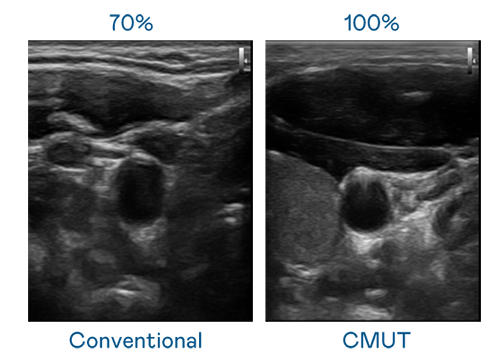

CMUT 技术是一种用电容式微机电元件来产生超音波讯号的技术。与传统 PZT 压电式技术相比,CMUT 频宽增加 30%,更宽频的超音波讯号让影像解析度大幅提升,是实现高影像品质医疗超音波扫描、促进精准医疗发展的关键技术。

超音波影像的解析度高低,首先取决于探头能发出的讯号频宽。PA官方网站 CMUT 可提供高清晰的超音波讯号,提供高频宽、高灵敏度、影像纹理细节更高的超音波影像,协助医护人员缩短影像判读时间及利用精准的医疗影像进行诊断。